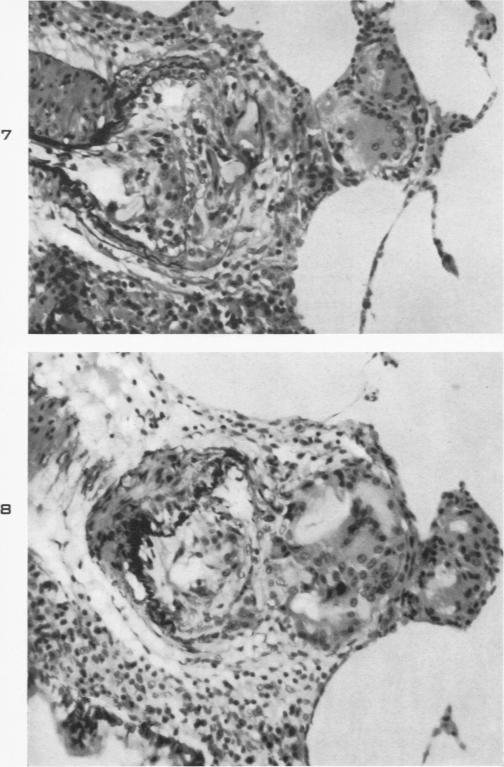

The reaction produced in the pulmonary arteries by emboli of cotton fibers.